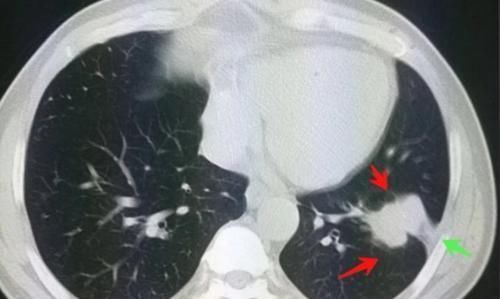

文章插图

上面4位病人,是浙江舟山肺癌研究中心的体检病人(曹捍波教授分享),都是早期肺癌,没有症状,通过体检发现的。

这种早期小病灶可以手术治愈!